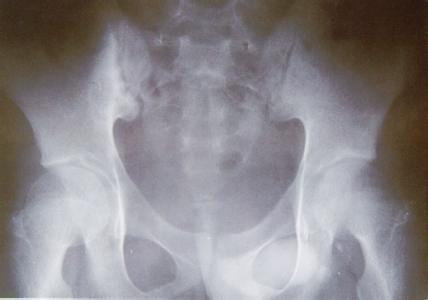

(图:X线片显示双侧骶髋关节间隙变窄)

骨盆ct片示:双侧骶髋关节隙变窄,髋臼缘欠规则,双侧股骨头形态尚正常。